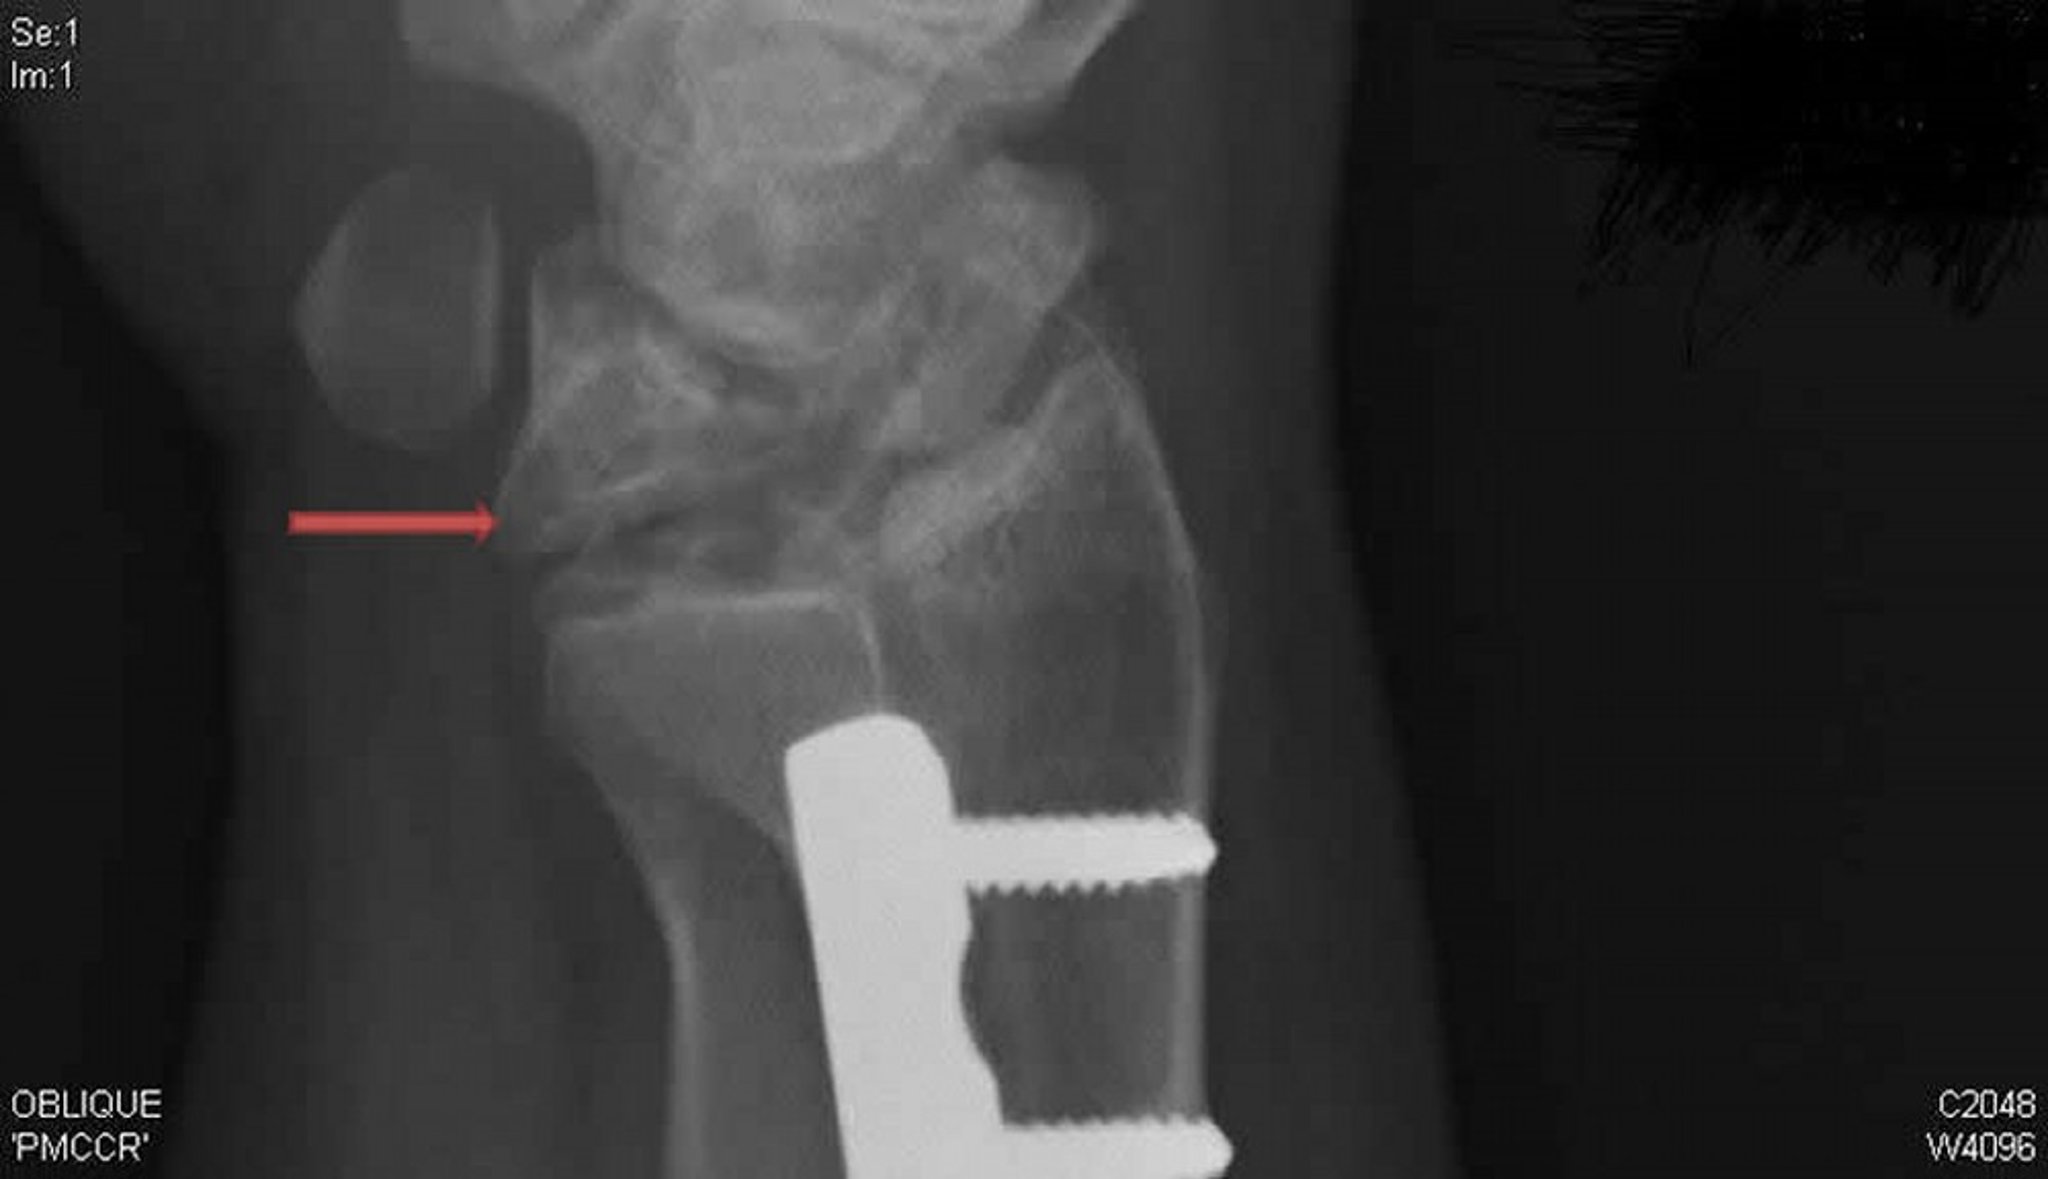

Kienböck Disease (Oblique Radiograph)

This oblique radiograph of the right wrist shows Kienböck disease. Note the collapse and fragmentation of the lunate bone (arrow), which was not apparent on the posteroanterior view.

Radiograph courtesy of David R. Steinberg, MD.